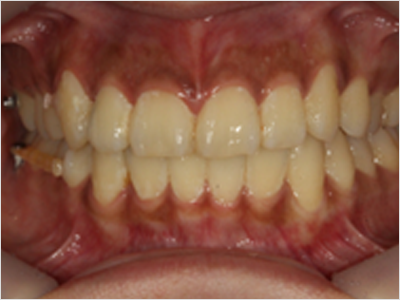

PROGRAM 03

돌출입 교정

입이 나와보이는 인상, 교정으로 부드럽게

입이 들어가도 앞니 각도 조절에 실패하면 옥니나 합죽이가 되어

심미성과 기능 모두 만족하기 어렵습니다.

개인별 분석을 통해 적절한 발치를 결정하고, 앞니를 자연스럽게 뒤로 배치해

안모 균형과 자신감을 되찾는 정밀한 돌출입 교정을 진행합니다.